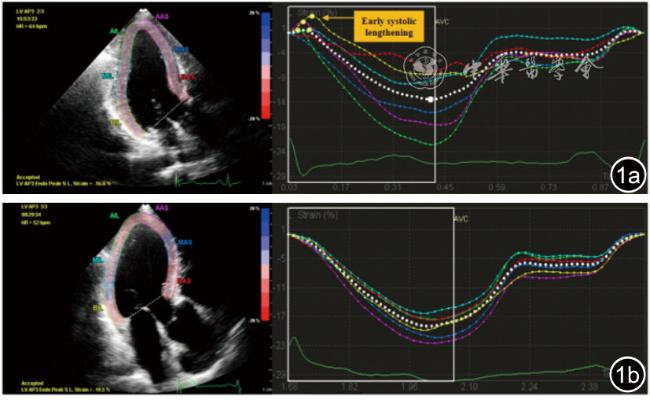

观察心肌在收缩早期是否出现矛盾伸展运动(图1),并测量其对应的收缩早期延长时间(the time to early systolic lengthening,EST),即舒张末期至收缩早期正向峰值应变的时间(图2)。若主动脉瓣关闭(aortic valve closure,AVC)后出现心肌缩短,即收缩后收缩(post-systolic shorting,PSS),则记录收缩后时间(the time to post-systolic shorting,PST)。计算左心室18节段均值得到整体EST(the time to global early systolic lengthening,GEST)、整体PST(the time to global post-systolic shorting,GPST),以及各冠状动脉灌注区心肌节段均值得到区域EST(the time to territorial early systolic lengthening,TEST)、区域PST(the time to territorial post-systolic shorting,TPST)。

图1 二维斑点追踪成像显示非ST段抬高型急性冠脉综合征患者左心室心尖三腔心切面的应变-时间曲线。图a为冠状动脉严重狭窄患者,部分心肌节段出现收缩早期延长(ESL);图b为非冠状动脉严重狭窄患者,不存在明显ESL